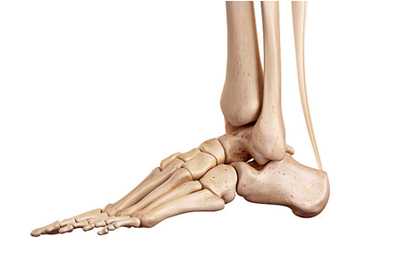

Поперечный сустав предплюсны или сустав Шопара состоит из таранно-ладьевидного и пяточно-кубовидного суставов. В обоих суставах есть фасетки овальной формы, ось которых проходит по наибольшему диаметру овала. В нейтральном положении стопы оси находятся под углом, а в положении пронации стопы оси становятся параллельными. В положении супинации угол между фасетками достигает максимума. Он больше, чем угол в нейтральном положении и чем угол в положении пронации. Головка таранной кости имеет выпуклую поверхность, а головка ладьевидной кости, которая сочленяется с ней, имеет, соответственно, вогнутую поверхность. Площадь фасетки таранной кости больше, чем площадь фасетки ладьевидной кости. В сагиттальной плоскости сустав Шопара расположен на расстоянии 32-36% от крайней точки пяточного бугра.

Рис. 1. Сустав Шопара с наружной и внутренней поверхности

Рис. 2. Сустав Шопара по тыльной поверхности стопы. Сустав включает в себя пяточно-кубовидный и таранно-ладьевидный суставы

Сустав Шопара укреплен несколькими связками. На тыльной поверхности сустава имеются 4 связки.